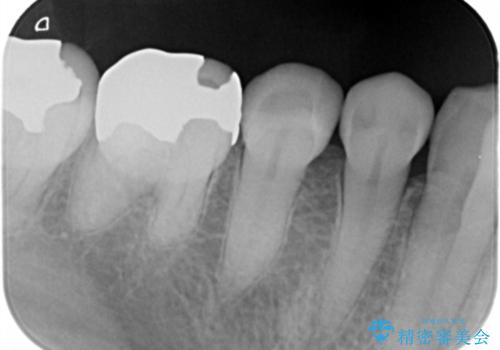

- 口を開けると銀歯が見えるのが嫌とのことで来院。

銀歯を外し、拡大鏡下で虫歯を全て取り除き、白い詰め物(e-maxインレー)にて治療することになりました。

まずは一つ治療したいとの事だったので手前の小臼歯から行いました。